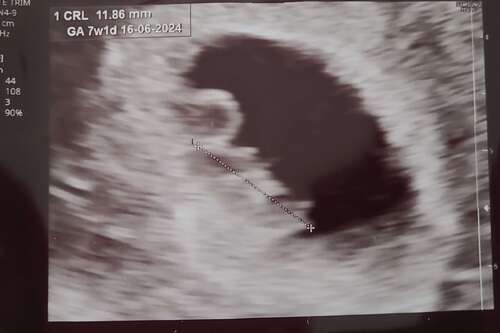

Vandaag een echo gehad met precies 6 wk. En we konden gelijk wat zien flikkeren😍 een mooi kloppend hartje ❤️